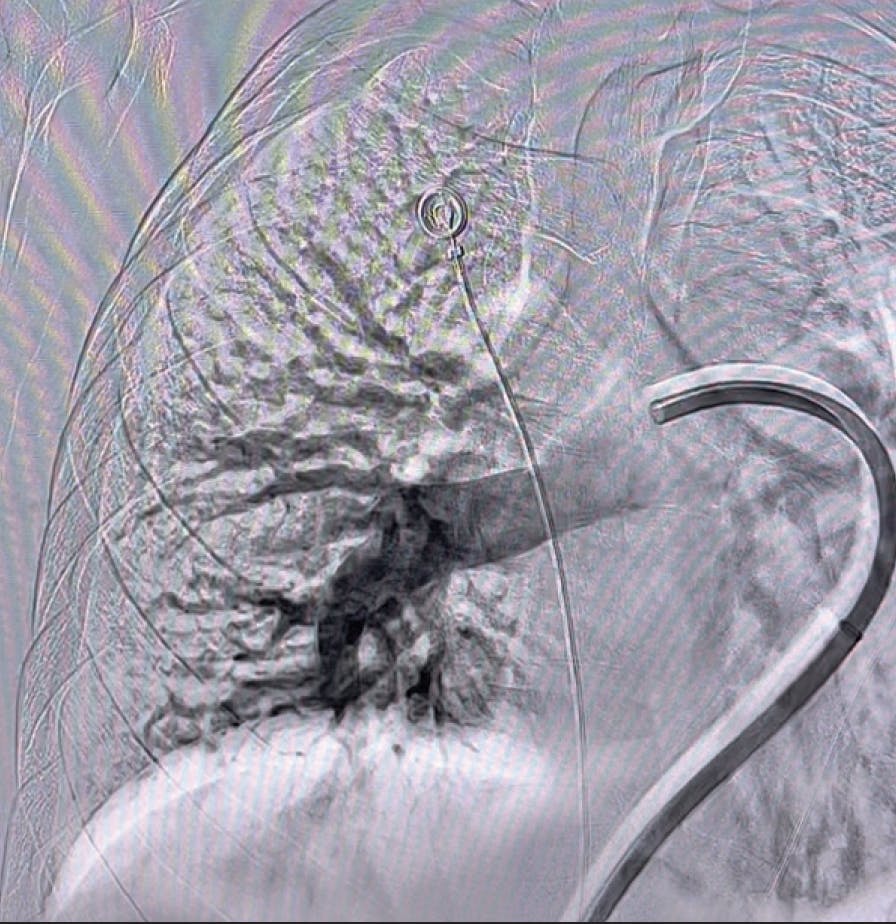

Based on evaluation, we decided to pursue aspiration thrombectomy utilizing Lightning Flash through a 16-F, 65-cm Gore DrySeal sheath (Gore & Associates). We achieved access in the right femoral vein. The device time was 17 minutes, and the total procedure time was 30 minutes (Figure 3, Figure 4, Figure 5, and Figure 6). At the conclusion of the case, the total EBL was 175 mL, the patient had BP of 112/67 mm Hg, HR of 65 bpm, and oxygen saturation of 99% on 3 L nasal cannula.

Figure 3. Post-thrombectomy lower right lobe angiogram.

Figure 4. Post-thrombectomy upper right lobe angiogram.

Figure 5. Post-thrombectomy left lobe angiogram.